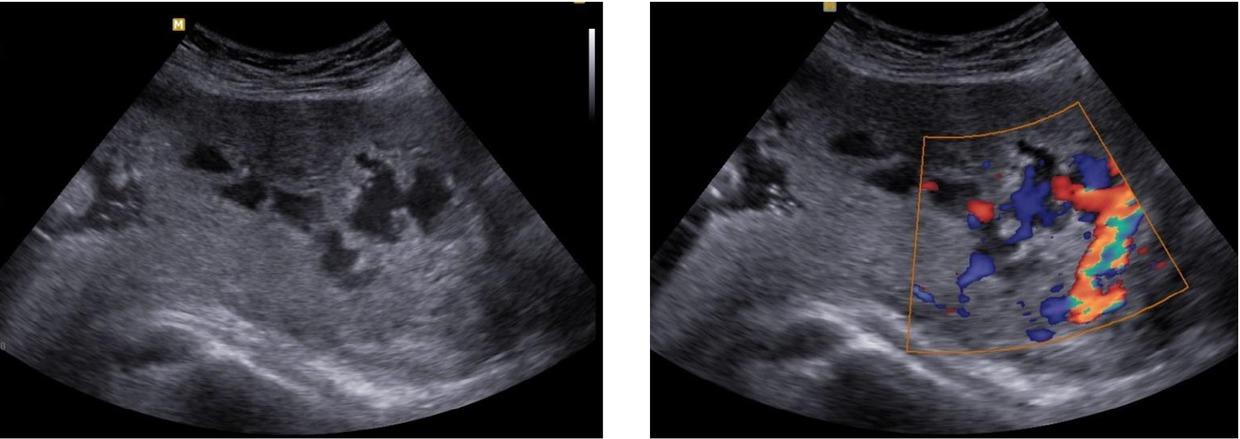

Fig. 1

Fig. 2